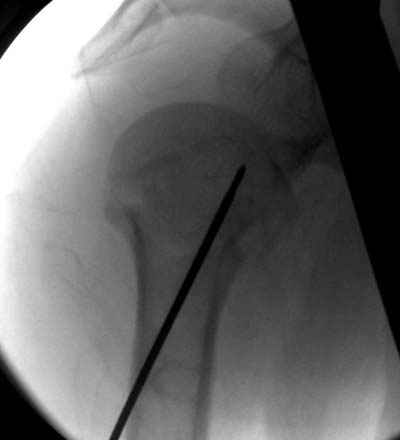

Здесь случай перелома-вывиха плеча, больному 56 лет, после "дважды" закрытой неудачной репозиции, опять же ургентно взяли в операционную, после полного общего обезболивания попытались сделать репозицию, и фиксацию провели спицами.

Больной находился в повязке, примерно напоминяющей косыночную, рекомендованы движения в локтевом суставе и маятниковые движения в плече, спицы удалены в три недели (были случаи миграции)

Больной амбулаторный, предупрежден на случай осложнения АВН головки.